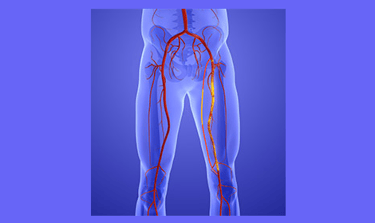

Peripheral Arterial Study

A peripheral arterial ultrasound analyses the flow through the arteries from the abdominal aorta- the main artery off the heart to the arteries at the foot. A blocked artery in the abdomen can stop the flow getting to the calf causing syptoms in the buttock, thigh or calf.

Leg Arteries

Ultrasound is used to assess the arteries of the leg for the presence of atherosclerosis - disease and narrowing of the arteries. Significant disease can cause pain with activity as the demand for blood supply to the leg muscles is increased and unable to be met.